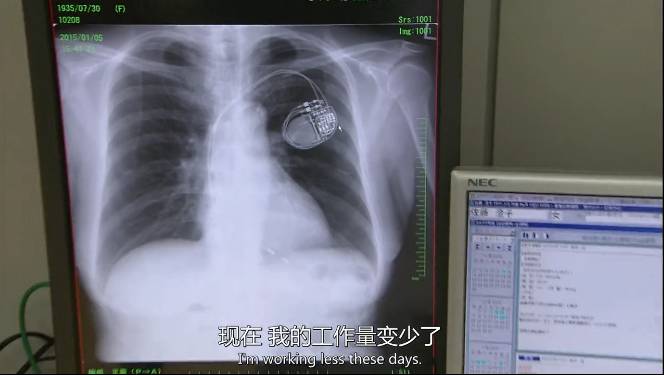

如今因为心脏问题,

妻子装上了心脏起搏器。难受的时候连胳膊都抬不起。

80岁高龄的她还是坚持每天到店里,“看到不整洁的货架,我就会不舒服。”